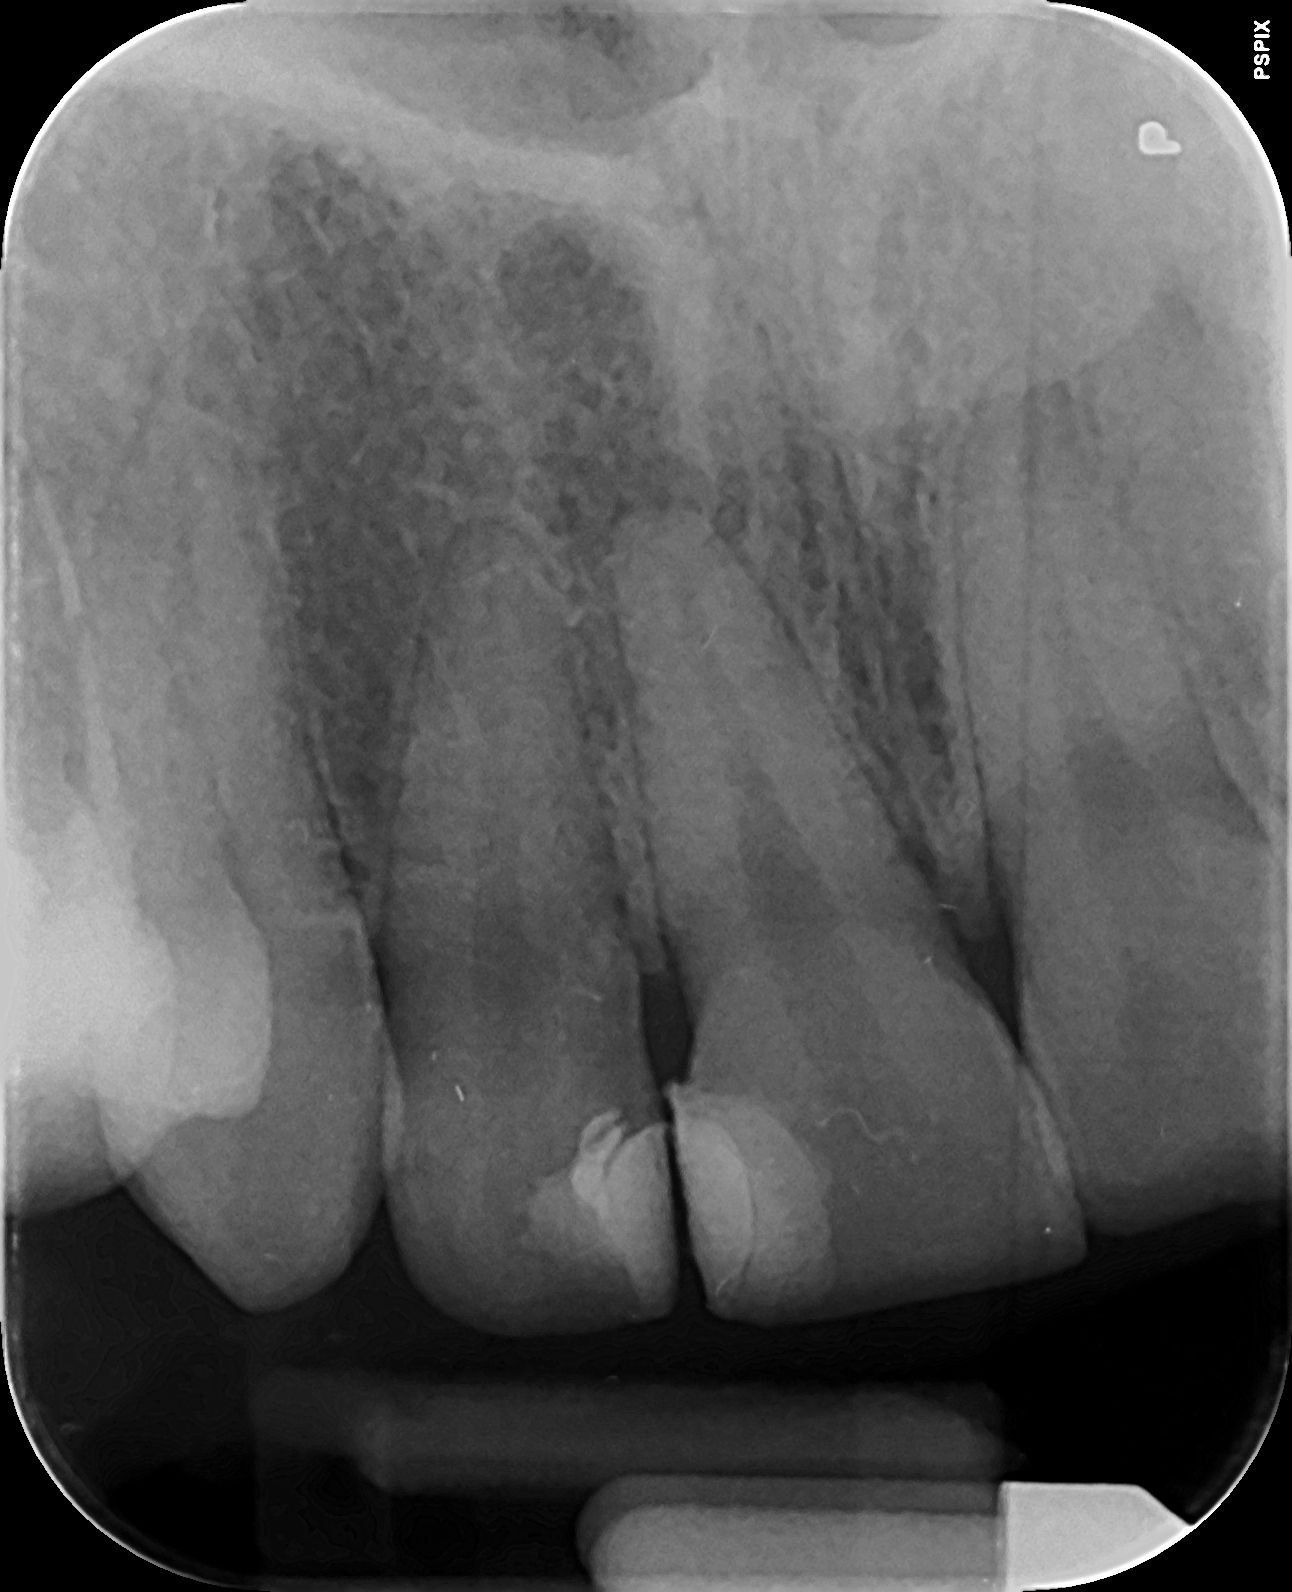

На снимката зъбът с чувствителността (снимката е отпреди да се махне старата пломба) е вторият отляво надясно. Старата пломба беше доста голяма, махната е само около половината отгоре (откъм по-малкия зъб). Там сякаш пломбата не е особено дълбока, затова не мога да си обясня на какво се дължи тази чувствителност...